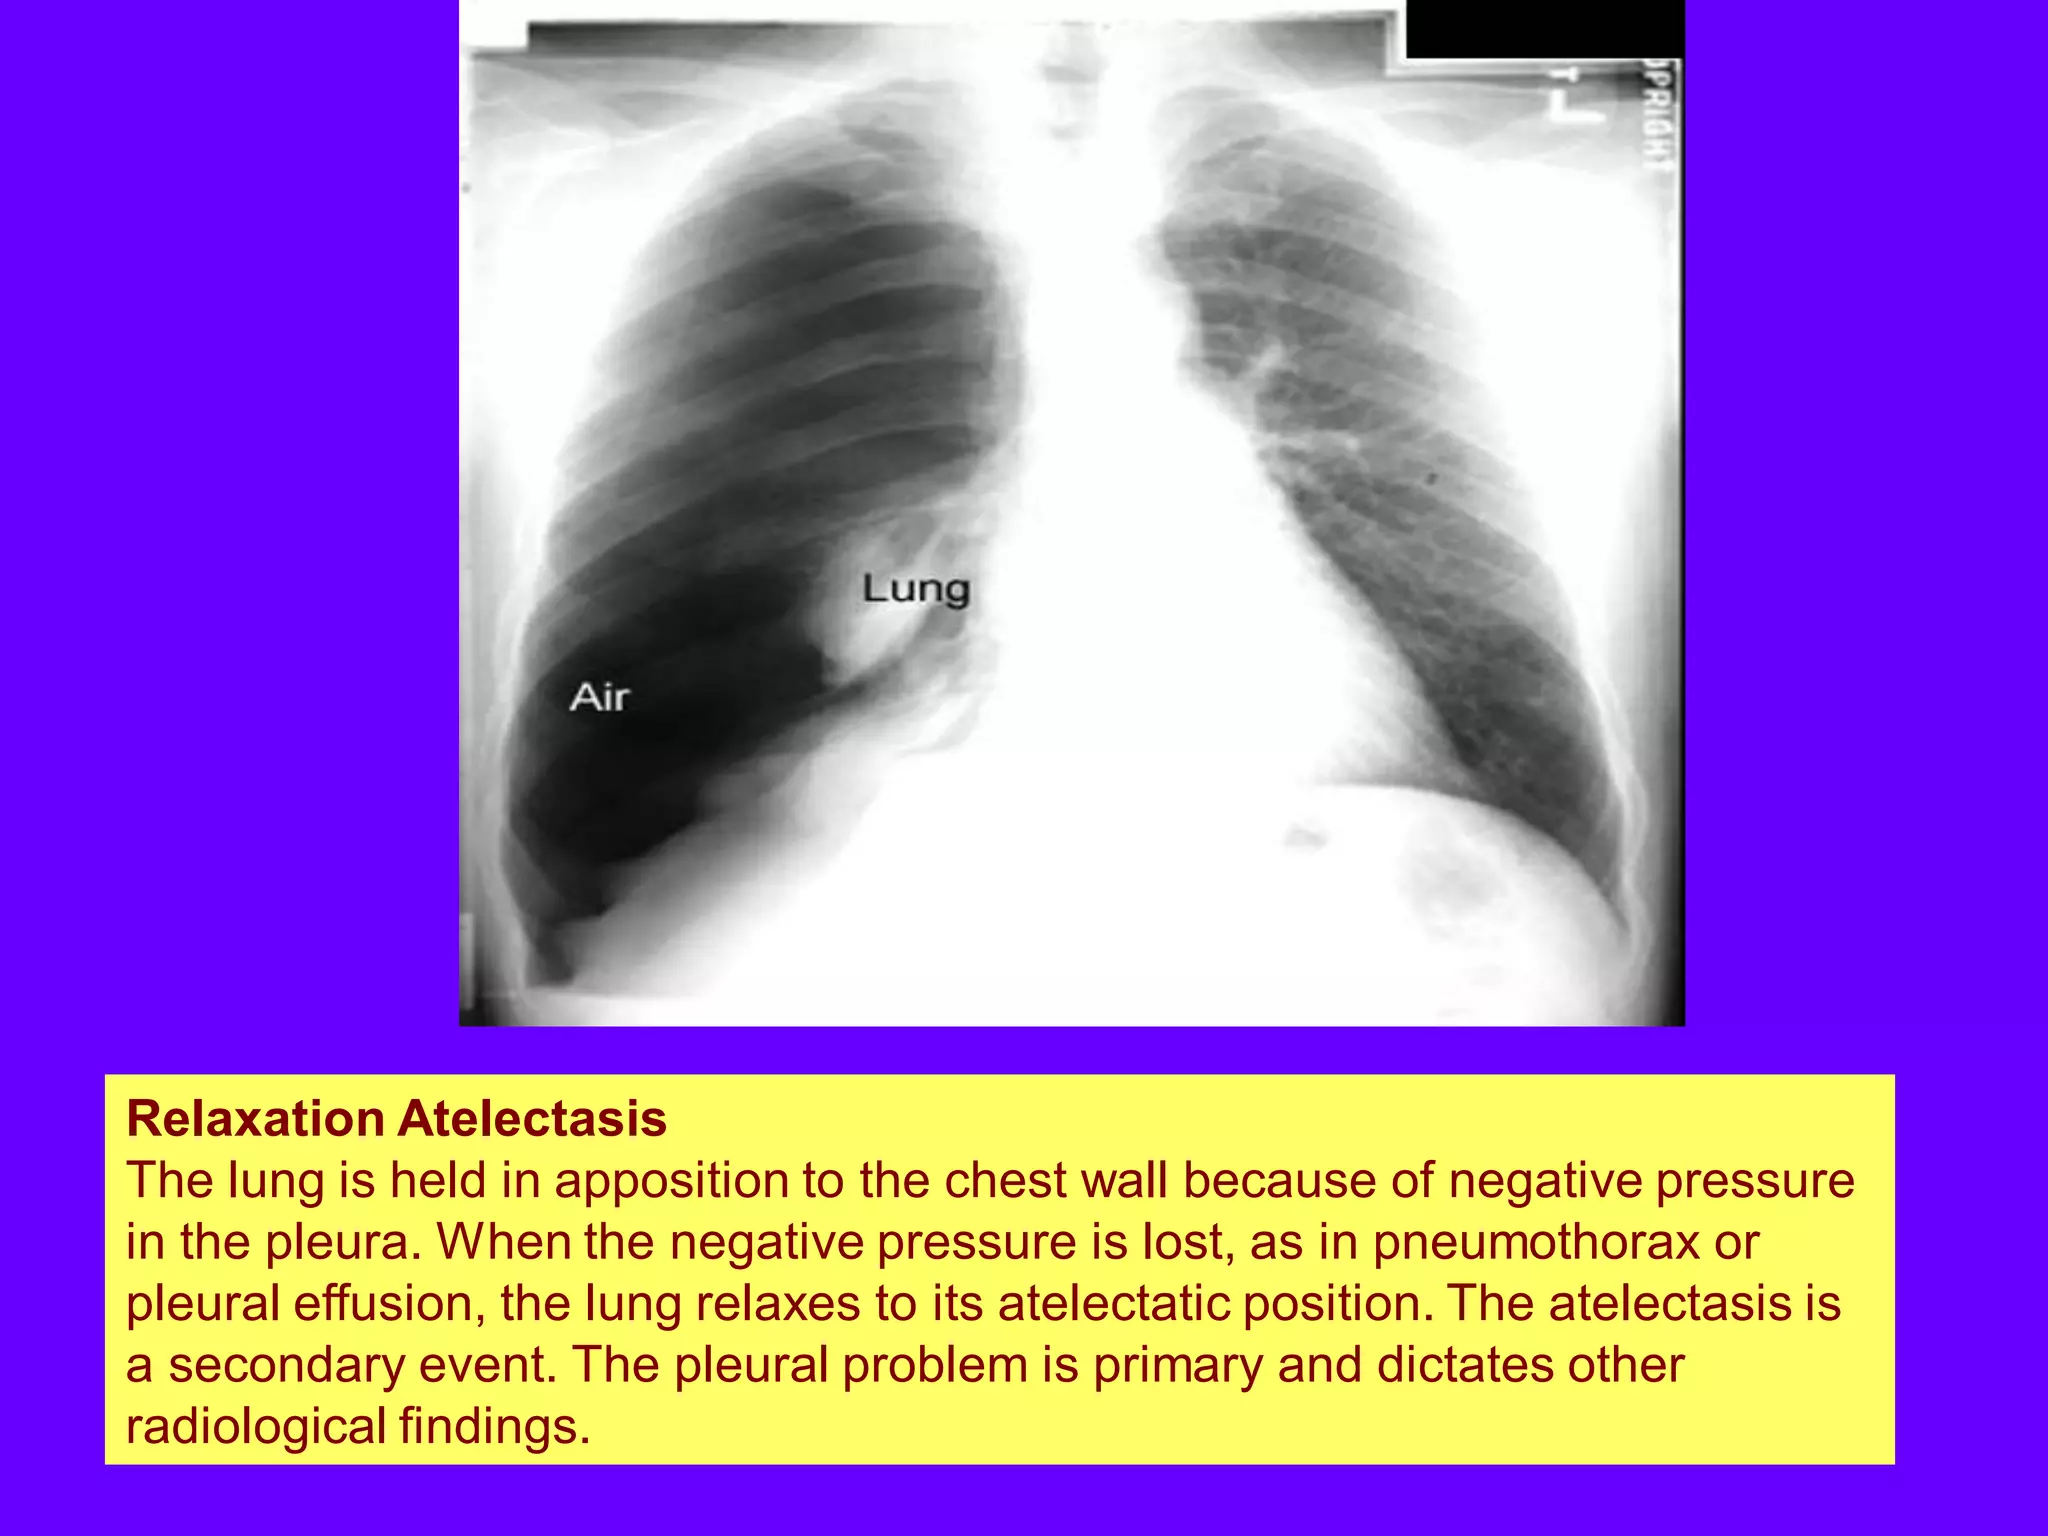

Relaxation Atelectasis

The lung is held in apposition to the chest wall because of negative pressure

in the pleura. When the negative pressure is lost, as in pneumothorax or

pleural effusion, the lung relaxes to its atelectatic position. The atelectasis is

a secondary event. The pleural problem is primary and dictates other

radiological findings.